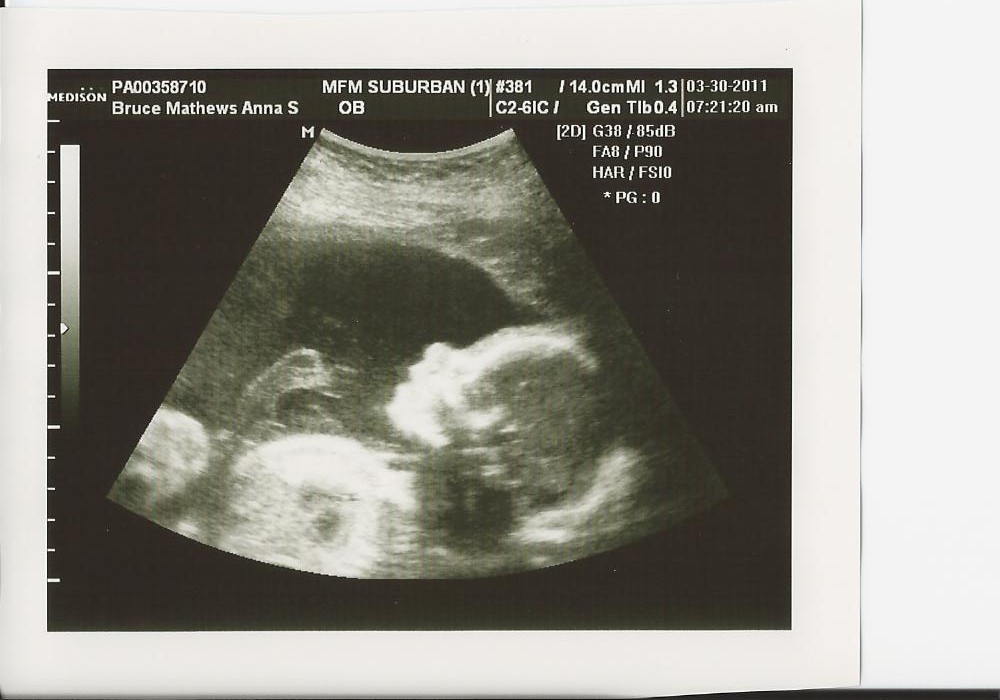

We had our appointment with the specialist this morning to check the progress of our sweet girl and check the status of my cervix... and we got great news! The baby is getting big and all of her organs are looking like they are developing well. They were also pleased that she is so active- and believe me she doesn't just turn it on for the camera, this little girl never sleeps! But I am so grateful to feel her moving so often. Maybe even more encouraging was the news the dr gave us about my body. My cervix is still over 4 centimeters and closed on both ends, even with the pressure of the baby moving against is. She shared with us today that because I am 22 weeks and the cervix is still such a great length, I now have LESS THAN a 5% chance of early labor (up to 28 weeks)!!! Josh and I were both relieved to hear this and I may get some sleep tonight! We are continuing to pray that the Lord sees fit to keep our little girl inside me for a while longer and we are so thankful for his faithfulness up to this point. Here are a few pictures of our sweet and somewhat cooperative little girl today...